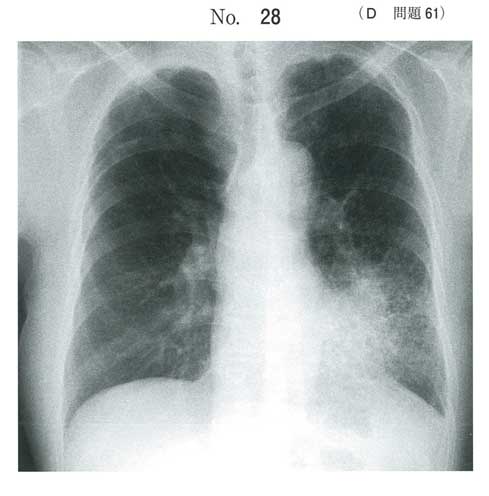

D問題

| タイトル:113D-61 | コメント数:6 | 割問 |

ADROPからは帰宅できるかなと

a 外来で治療できるとは思います。しかし、臨床家はレアケースを経験すればするだけ迷うかもしれませんね

aだと思いますが、断定するのは少し難しいところです。

ADROPやCURB65では余裕で外来OKですが、PSIを用いると入院適応となります(年齢、BUN、血糖とついでに肝障害も)。実臨床だと入院も並べて提示し、選んでもらう形になると思います。

a以外の選択肢の説明は適当ではないかな、と。

同じようなケースで入院させたことはないですね…

ADROPの問題なので、まずはAのはなしを。Aの説明をした上で入院希望があればさらに傾聴といったところでしょうか。

まぁ国試的にはa

年齢もバイタルも臨床症状も大丈夫そうな情報ばかり

炎症反応は高いですが肺炎球菌ですし

実際には入院も提示して、希望あれば

入院加療でも全然いいと思います